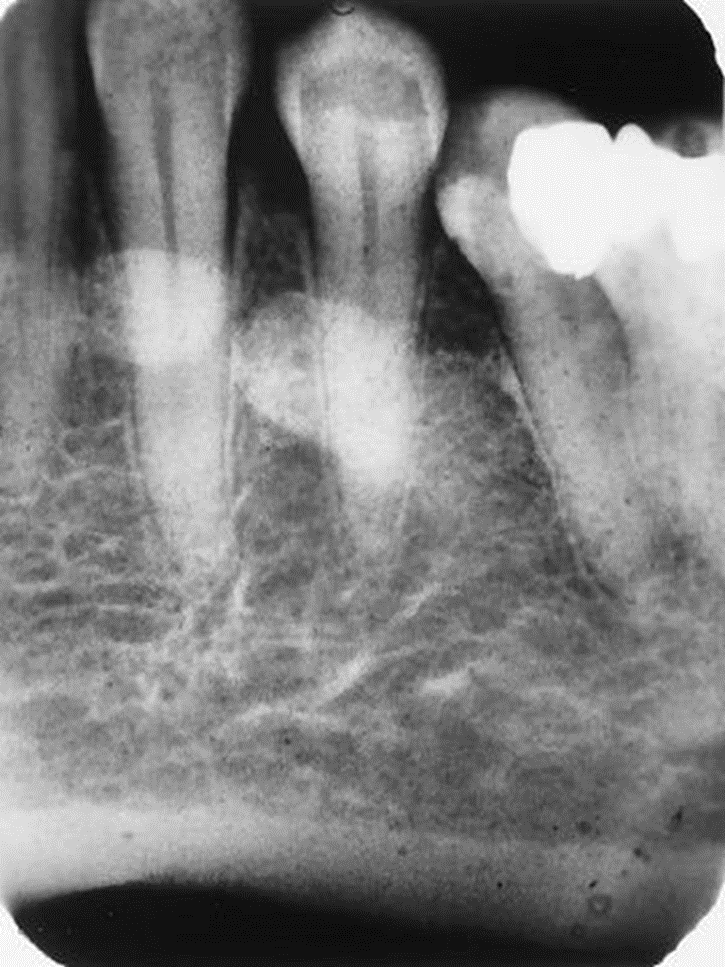

1. Mary is a 67-year-old who was referred to the periodontist. As part of the adiographic examination, this small radiolucent lesion was detected. The teeth were vital. Considering the patient’s age and the location, size, and clinical findings, what is your diagnostic impression?